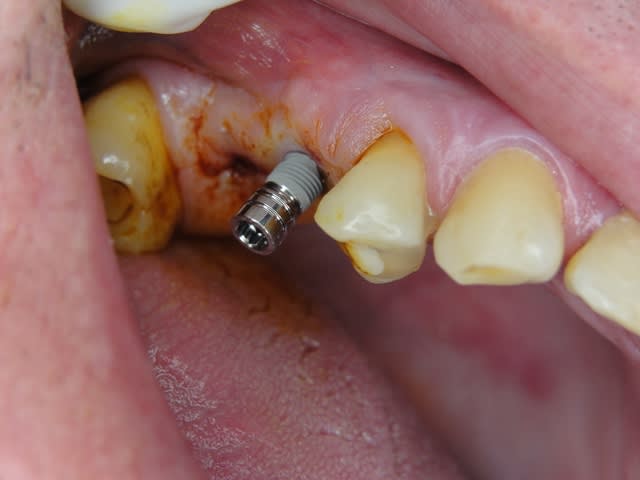

Pour ceux que ca interessent, et parce qu on a m a demandé des cas supplémentaires dans le sujet 23 implants rehabilitation totale, voici un autre cas d implantation immédiate avec la technique minimalement invasive et condensation grace aux forets.

Le patient a reçu un traitement il y a dix ans dans le maxillaire et dans le 4eme quadrant.Comme on peut le voir j´ai du extraire quelques dents au maxillaire: 35 37 et 45.

Le septum de la 37 a été foré avec un foret conique 3 faces.

J ai planté à 60 Ncm sans fracturer le septum.Juste après l opération , les prep caps en zircon ont été cémenté.La restauration définitive 34 jusqu` à 37 été fixé 2 semaines après l implantation avec implantlink (detax). Après un an, le bridge a été retiré facilement pour voir l´état de la gencive et faire une radio de contrôle.On la re ossifiction est satisfaisante et que la gencive "aime" le zircon.

Le bridge a ensuite été recémenté sans correction nécessaire du bridge.